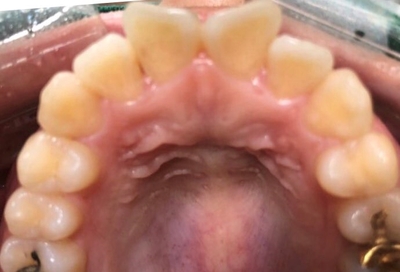

그래서 저희 시청역 치과 연세예감치과에서는

대문니 (앞니) 2개를

첫날: 하루만에 원데이 신경치료를 두 치아 모두 다 한 후

신경치료 한 후 바로 그날 치아를 다듬어서

둘째날 : 다음 내원 때 지르코니아크라운을 만들어 드렸습니다.

단 2회 내원만에 과거 모습에서 이렇게 되신건데요

요렇게 아래 사진처럼 고르게 되셨습니다.

물론 교정이 더 좋은 방법이긴 하지만

환자분은 2번 내원만에(단 일주일만에)

고른 이를 가지게 되셨습니다!

환자분이 말씀하셨듯이 철길 안깔고도요!